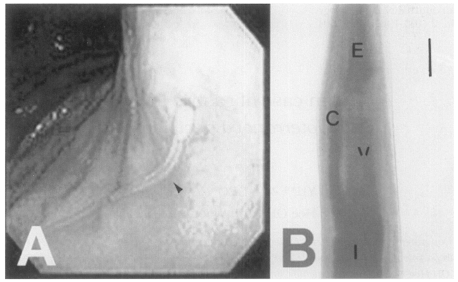

The patient, residing in Chungju-shi, Chungchungbuk-do, was a 34-year-old man. He was admitted to the Department of Internal Medicine in Konkuk University Hospital on Dec 13, 1994. The chief complaint of the patient was prickling epigastric pain and nausea, which developed two days after eating raw marine fish at Chonan-shi, Chungchungnam-do. He was diagnosed as having gastroenteritis. On physical examination, rebound tenderness was positive at the epigastrium, and no specific abnormal findings were revealed from laboratory examinations. Gastrofiberscopic exmaination was performed under the impression of anisakiasis. A long white, yellowish nematode larva invading the gastric mucosa was found in the fundus region and removed (Fig. 1A).

The recovered worm was fixed in 10% formalin, cleared in alcohol glycerine and mounted in glycerin jelly. The mounted specimen was observed and measured under a light microscope. The nematode larva is slender and the mouth is surrounded by three lips without a boring tooth. The intestinal cecum is stretched anteriorly to the level of one-third portion of the ventriculus (Fig. 1B). The tail is conical shaped, and reproductive organs are not developed.

The worm measured 34.50 mm long (L) and 0.84 mm wide (W). The total length of the esophagus (E) was 3.38 mm. The ventriculus (V), 1.25 mm long, is directly connected to the muscular esophagus (M), 2.13 mm long, without any appendage. The cecum (C) 1.13 mm, tail 0.12 mm. The morphological indices of the worm are as follows; α(L/W) = 27.60; β1(L/E) = 10.21; β2(L/M) = 15.81; β3(L/V) = 27.60; γ(L/C) = 30.53. From the morphological characteristics and indices, the worm is identified as the 3rd stage larva of P. decipiens.

The present worm was diagnosed as P. decipiens based on the absence of ventricular appendage but the presence of an intestinal cecum. In addition, the worm has a cecum reaching beyond the one third anterior level of ventriculus and a mucron at posterior end, suggesting the 3rd stage.